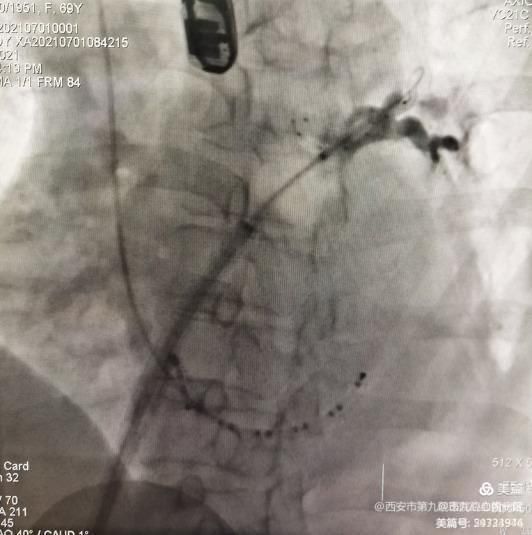

术前行肺静脉+左心房CTA、食道心房超声排除左心耳血栓,并充分了解左心耳的形态、大小。首先进行全麻,待患者全麻完成后正式开始手术。常规穿刺放标测电极,一次房间隔穿刺成功,进行左右肺静脉造影。依次进行左上、左下肺静脉冷冻消融:

继之进行右上、右下肺静脉冷冻消融: